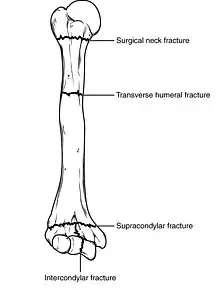

Classification

Fractures of the humerus are classified based on the location of the fracture and then by the type of fracture. There are three locations that humerus fractures occur: at the proximal location, which is the top of the humerus near the shoulder, in the middle, which is at the shaft of the humerus, and the distal location, which is the bottom of the humerus near the elbow.[9] Proximal fractures are classified into one of four types of fractures based on the displacement of the greater tubercle, the lesser tubercle, the surgical neck, and the anatomical neck, which are the four parts of the proximal humerus, with fracture displacement being defined as at least one centimeter of separation or an angulation greater than 45 degrees. One-part fractures involve no displacement of any parts of the humerus, two-part fractures have one part displaced relative to the other three; three-part fractures have two displaced fragments, and four-part fractures have all fragments displaced from each other.[13][14][3] Fractures of the humerus shaft are subdivided into transverse fractures, spiral fractures, "butterfly" fractures, which are a combination of transverse and spiral fractures, and pathological fractures, which are fractures caused by medical conditions.[12] Distal fractures are split between supracondylar fractures, which are transverse fractures above the two condyles at the bottom of the humerus, and intercondylar fractures, which involve a T- or Y-shaped fracture that splits the condyles.[7]